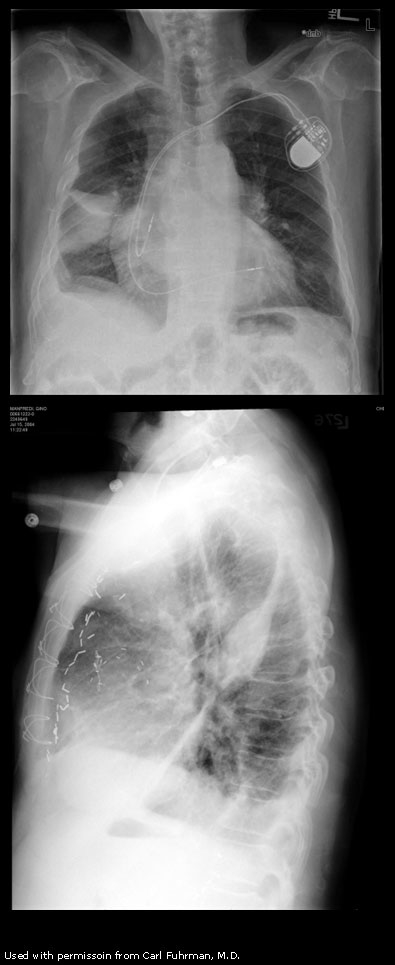

What’s going in in this CXR?

This is a postpneumonectomy patient, with the surgical clips in place.

This was taken POD1 following pneumonectomy. Over the next months, this space will slowly fill with fluid, and then over the following 3 months it will gradually fibrose. The heart and mediastinum will then shift towards this side due to myofibroblast contraction.

The patient will also be missing the 5th or 6th rib, taken as part of the procedure, and surgical clips will be present.